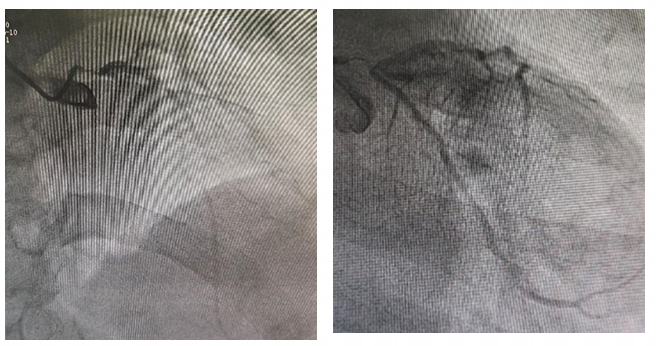

造影结果

LM:全程弥漫狭窄85-90%。

LAD:弥漫斑块浸润,开口狭窄80%,中段弥漫狭窄50-70%。

LCX:弥漫斑块浸润,开口狭窄80%,中段弥漫狭窄60-70%。

RCA:近段局限性狭窄80%,中远段可见弥漫斑块浸润。

▲ 最后造影结果理想满意